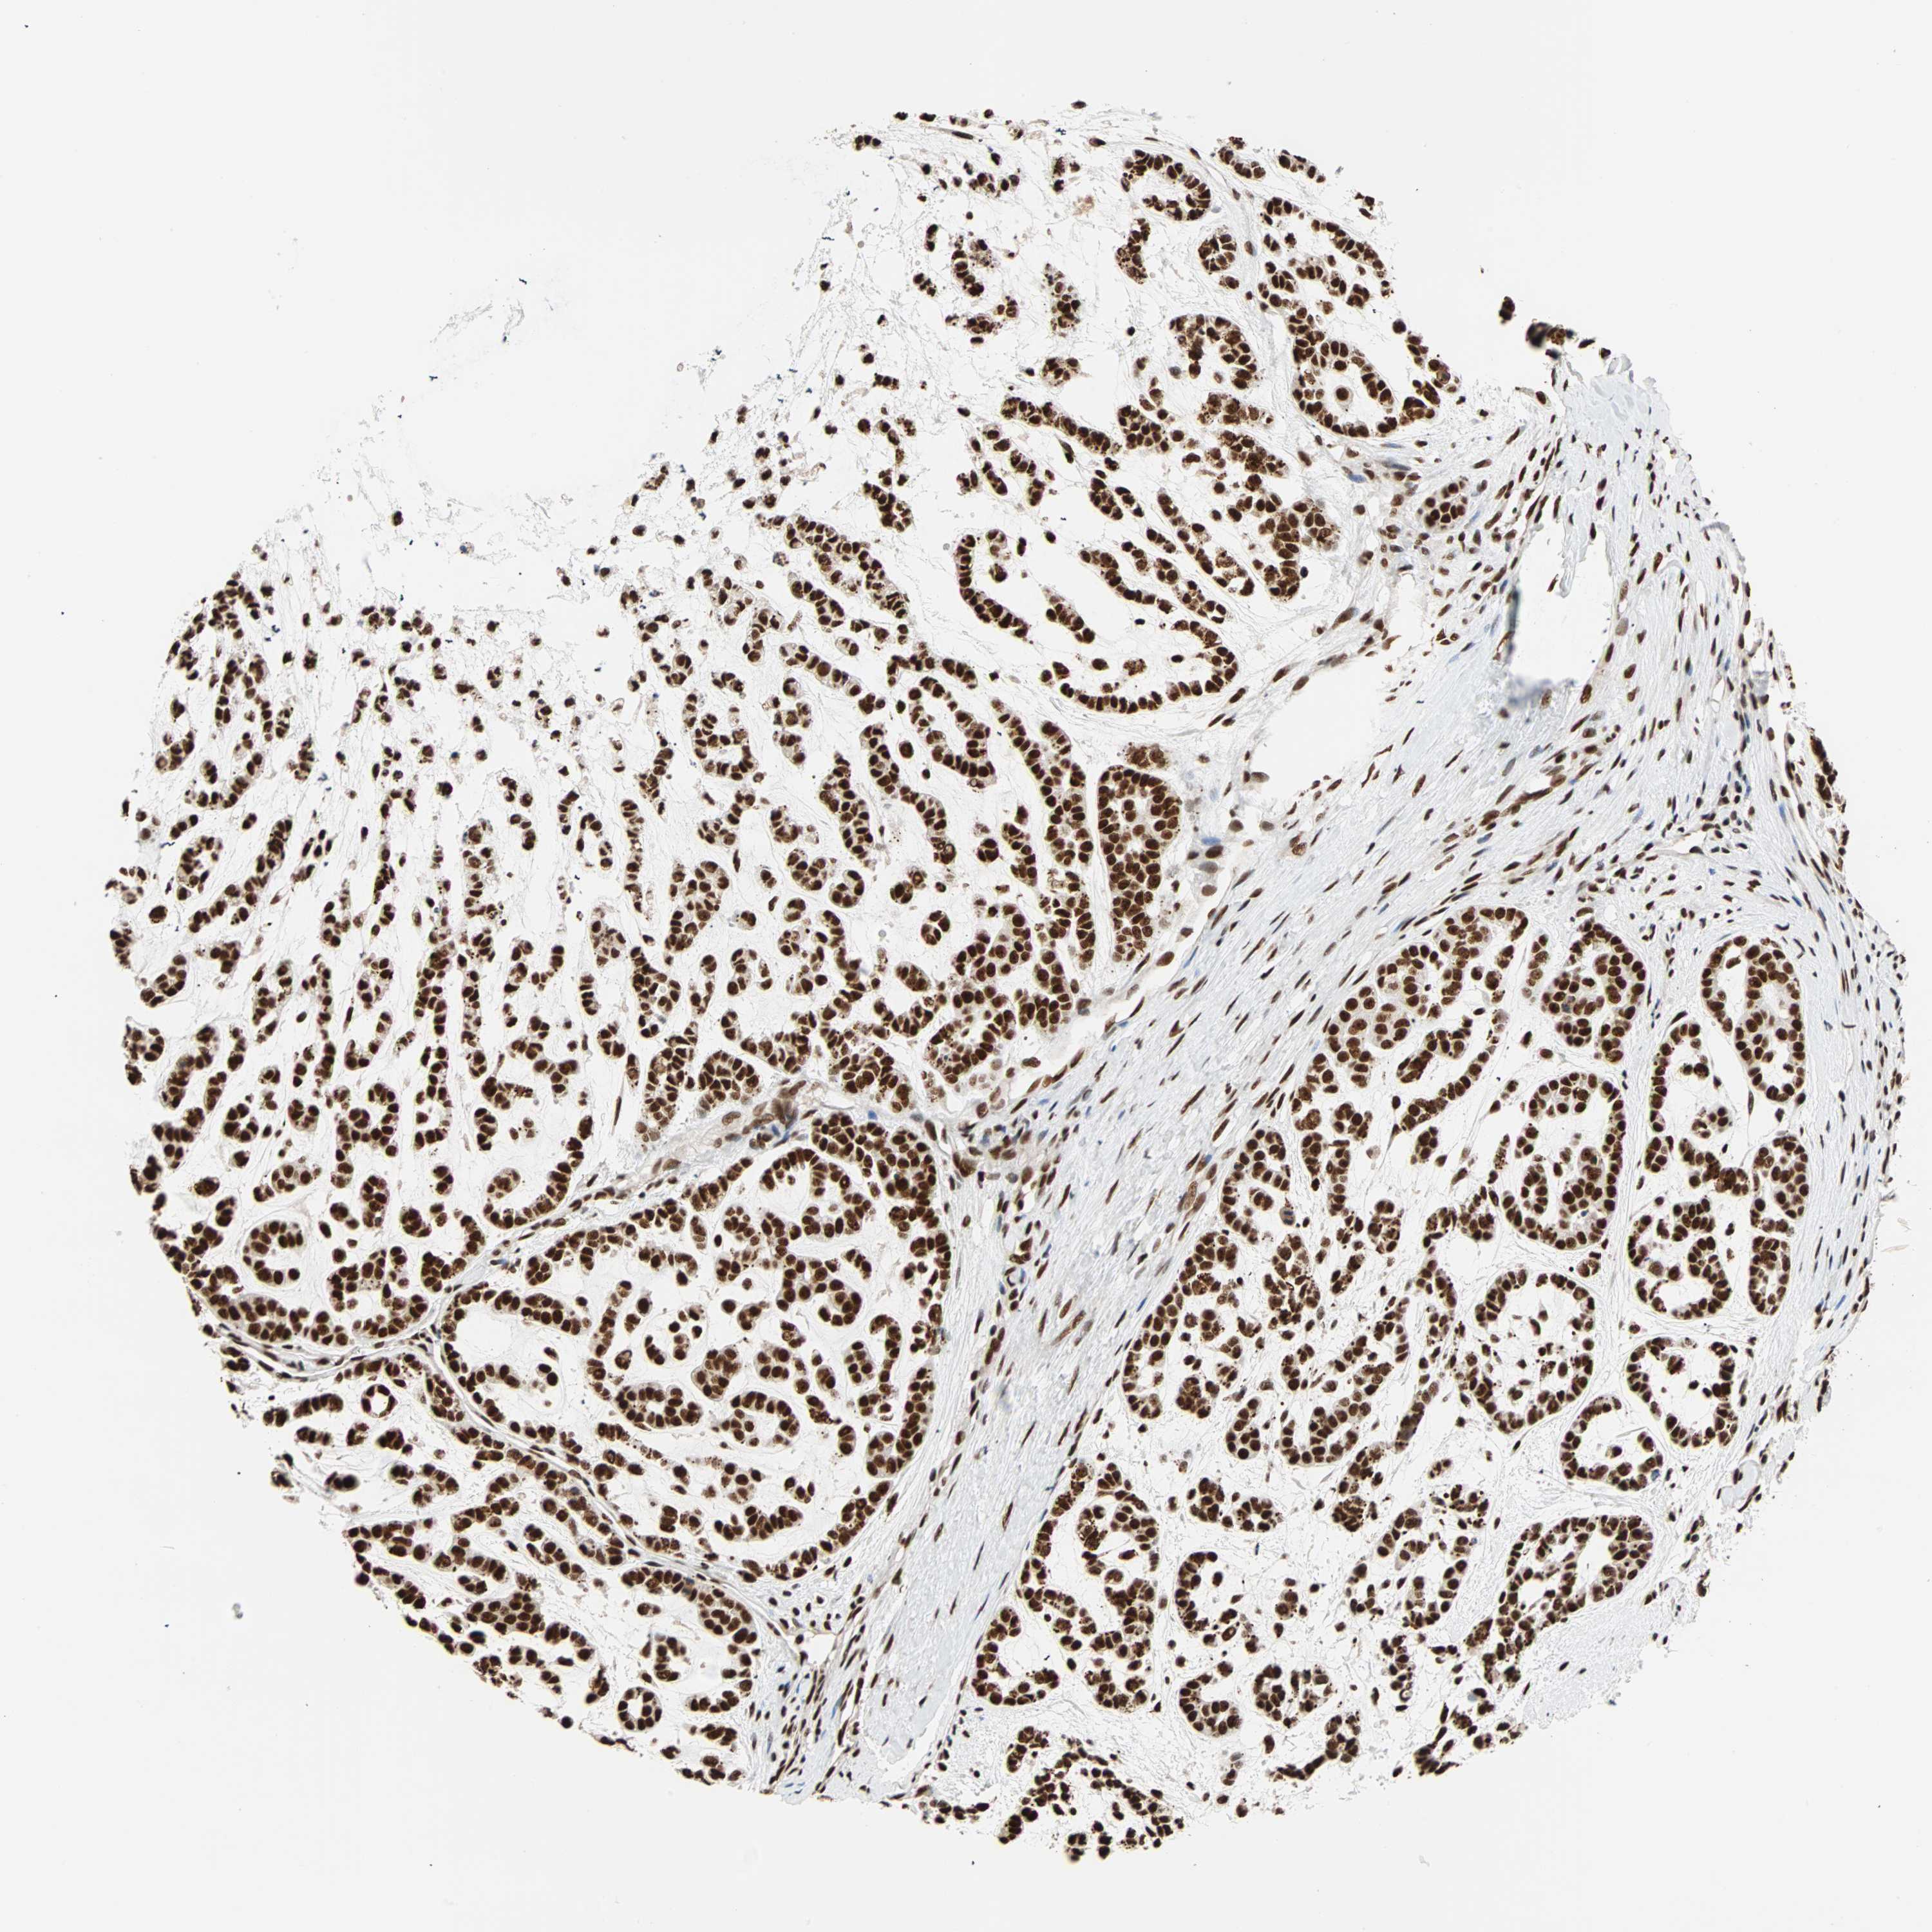

HEAD AND NECK CANCER - Protein expressioni

A mouse-over function shows sample information and annotation data. Click on an image to view it in a full screen mode. Samples can be filtered based on level of antibody staining by selecting one or several of the following categories: high, medium, low and not detected. The assay and annotation is described here.

Antibody stainingi

Antibody staining in the annotated cell types in the current human tissue is reported as not detected, low, medium, or high, based on conventional immunohistochemistry profiling in selected tissues. This score is based on the combination of the staining intensity and fraction of stained cells.

Each image is clickable and will lead to virtual microscopy that enables deeper exploration of all samples and also displays staining intensity scores, fraction scores and subcellular localization as well as patient and tissue information for each sample.

Antibody HPA007484

Staining

High

Medium

Low

Not detected

Intensity

Strong

Moderate

Weak

Negative

Quantity

>75%

75%-25%

<25%

None

Location

Nuclear

Cytoplasmic/membranous

Cytoplasmic/membranous,nuclear

Squamous cell carcinoma, NOS